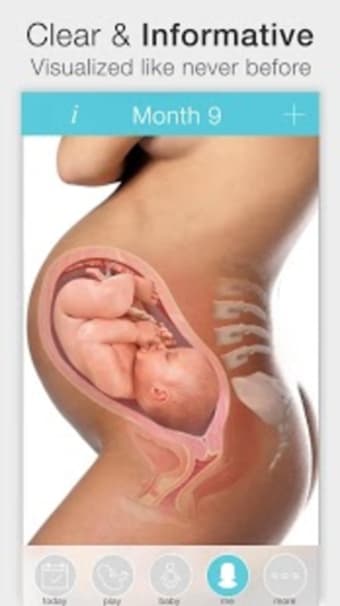

아기의 발달과 진행 상황을 추적하고 손끝에서 올바른 정보를 얻을 수 있는 좋은 방법입니다.